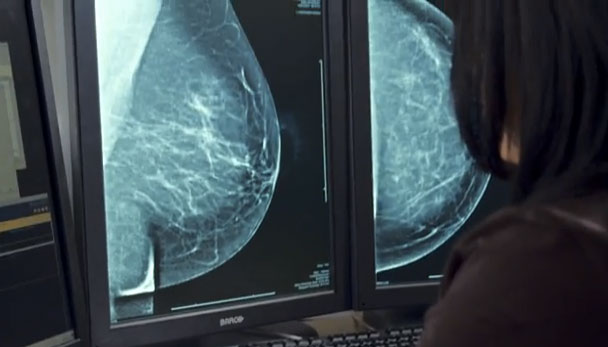

Experiencia del examen